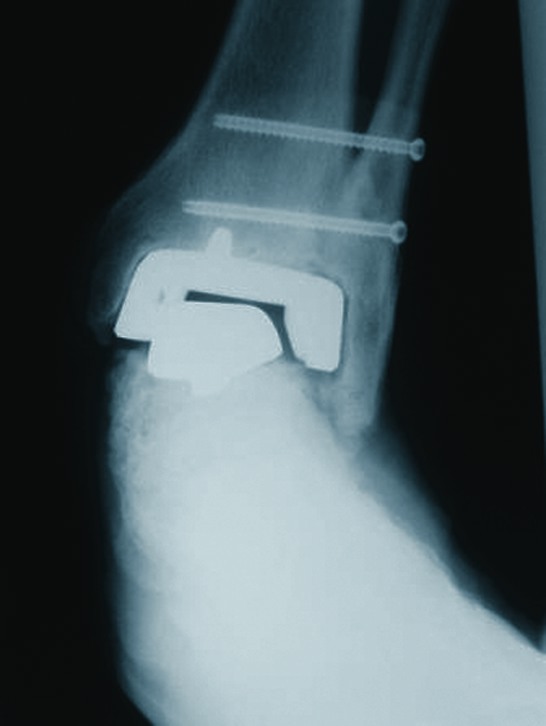

Case Study: When An Ankle Implant Arthroplasty Fails

In this case, a patient presented with significant failure of a previous ankle implant arthroplasty. In the above photo, note the valgus and subsidence of the talar component. One can also see the loosening of the tibial component and the probable non-union of the syndesmosis.

The surgeons used an isolated medial approach. Note the large defect after removal of the implant in the above photo.